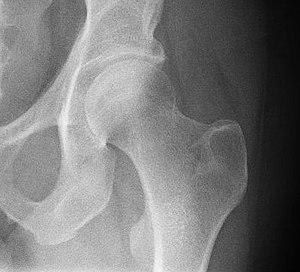

Das Hüftgelenk (lat. Articulatio coxae) ist nach dem Kniegelenk das zweitgrößte Gelenk der Säugetiere. Der Oberschenkelknochen (Femur) und das Becken (Pelvis) bilden dabei die knöchernen Gelenkpartner. Es ist vor allem bei den (menschlichen) Fortbewegungsarten des Gehens, bei dem es im Gegensatz zum Laufen keine Flugphase gibt, eingebunden.

Der Oberschenkelknochen bildet am oberen Ende einen großen kugelförmigen Kopf (Caput femoris). Dieser stellt eine relativ regelmäßig gekrümmte Zwei-Drittel-Kugel mit einem Radius von durchschnittlich 2,5 Zentimetern dar. Lediglich der gelenknahe (proximale) Pol formt eine plane Fläche um die Einziehung des Oberschenkelknochenkopfes (Fovea capitis femoris), um die zu übertragende Last von einem Punkt auf einen Ring zu verschieben. Der Oberschenkelknochenkopf ist durchgehend von hyalinem Knorpel überzogen, weist in seinen Hauptbelastungszonen jedoch eine besonders ausgeprägte Schicht von etwa 2,5 bis 3,5 Millimetern auf. Zum Oberschenkelknochenhals (Collum femoris) hin nimmt die Dicke sukzessiv ab.

Am Aufbau des Gegenstückes, der Hüftgelenkpfanne (Acetabulum), sind alle drei Beckenknochen beteiligt: Das Dach wird vom Darmbein (Os ilium) gebildet, das Schambein (Os pubis) begrenzt vorne (ventral) und das Sitzbein (Os ischii) hinten-unten (dorsokaudal) den Rand des Beckens mit seiner Vertiefung, das so genannte Acetabulum („Essignäpfchen“).

Stellt man sich die Pfanne als hohle Halbkugel vor, beträgt ihr Radius beim Menschen je nach Körpergröße etwa 2,7 Zentimeter. Eine bogenförmige Faserknorpellippe (Labrum acetabuli bzw. Limbus acetabuli) geht jedoch stellenweise über den Äquator der Halbkugel hinaus und umgreift regelrecht den Oberschenkelknochenkopf. Daher spricht man beim Hüftgelenk auch von einem Nussgelenk (Sonderform des Kugelgelenkes). Zum Schambeinloch (Foramen obturatum) ausstrahlend ist die Pfannenlippe hingegen unterbrochen (Incisura acetabuli), sodass sie eine halbmondförmige Gestalt annimmt. Dieser unterbrochene Teil der Pfanne wird von einem Querband (Ligamentum transversum acetabuli) überbrückt.